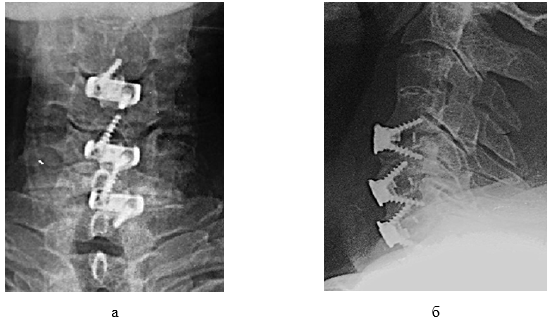

Через 2 часа после операции пациент отметил нарастание силы в руках, появление всех видов чувствительности на туловище и нижних конечностях. Неврологический статус через 1 сутки после операции: ВАШ 1 балл, ASIA - ДФ 56 баллов, ТЧ 94 балла, БЧ 98 баллов; самопроизвольное мочеиспускание восстановилось полностью; по Frankel группа здоровья В. Дренаж удален и выполнена контрольная рентгенография шейного отдела позвоночника (рис.3).

Рис. 3. Фото послеоперационных рентгенограмм шеи пациента мужского пола 71 года: а – прямая проекция; б – боковая проекция.

Составлено авторами по результатам данного исследования

На рис. 3 видно, что задние остеофиты удалены, межтеловые кейджи установлены корректно, мальпозиции винтов нет, высота диска и задняя позвонковая линия восстановлены.